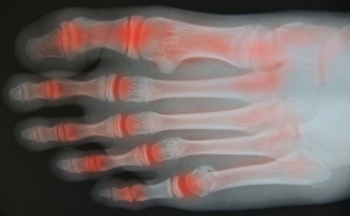

In order to diagnose your bunion, your podiatrist may ask about your medical history, symptoms, and general health. Your doctor might also order an x-ray to take a closer look at your feet. Nonsurgical treatment options include orthotics, padding, icing, changes in footwear, and medication. If nonsurgical treatments don’t alleviate your bunion pain, surgery may be necessary.

A podiatrist knowledgeable in foot structure and biomechanics will be able to quickly diagnose bunions. Bunions must be distinguished from gout or arthritic conditions, so blood tests may be necessary. The podiatrist may order a radiological exam to provide an image of the bone structure. If the x-ray demonstrates an enlargement of the joint near the base of the toe and a shifting toward the smaller toes, this is indicative of a bunion.

Signs of Rheumatoid Arthritis

Many people begin to develop rheumatoid arthritis, or RA, when they reach their 30s or 40s. This disease is an autoimmune disorder in which the body’s immune system actually attacks the body's own tissues. This can cause pain in the joints, including those of the ankles, feet, and toes. Early symptoms of rheumatoid arthritis include fatigue, stiffness, and inflammation in the joints. Pain is generally worse when you first get up in the morning. Swelling in the lining of the joints causes pain and redness, and in most cases, affects both feet. Going up and down stairs becomes more difficult, and RA can interfere with carrying out daily activities. As rheumatoid arthritis progresses, nodules or hardened bumps may form in the joints. Eventually, the nearby bones and cartilage are affected, causing more visible deformities. In some cases, RA can harden the arteries, thereby increasing the risk of heart-related problems. For help with issues of rheumatoid arthritis in the feet, it is suggested that you consult a podiatrist.

Arthritis is a joint disorder that involves the inflammation of different joints in your body, such as those in your feet. Arthritis is often caused by a degenerative joint disease and causes mild to severe pain in all affected areas. In addition to this, swelling and stiffness in the affected joints can also be a common symptom of arthritis.